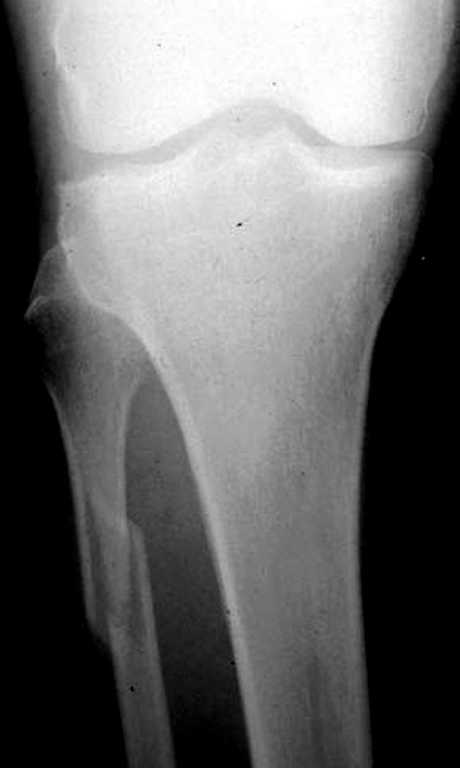

При проксимальных переломах малоберцовой автоматически необходимо подозревать повреждение синдесмоза - Maisonneuve Fracture.

Описанное в 1840 году Maisonneuve повреждение характеризуется тем, что при фиксированной наружной ротации стопы повреждается передняя фибуло-тибиальная связка, часть синдесмоза, с переломом медиальной лодыжки и без, дальше разрыв продолжается по межкостной мембране и спиральный или косой перелом малоберцовой происходит выше.

На прямой проекции можно увидеть расширенную медиальную щель, и на мортизе укорочение малоберцовой.